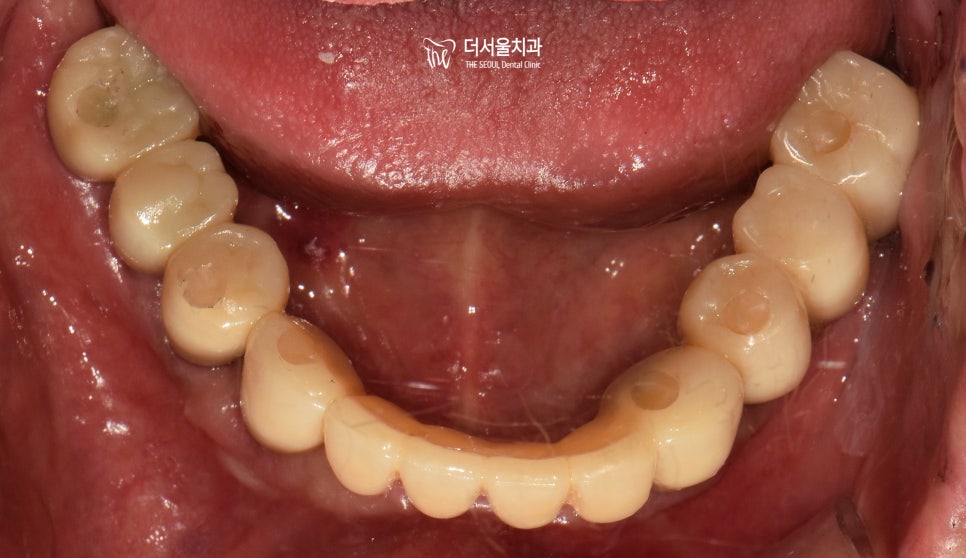

이제 최종 보철 제작만을 앞두고 있는데요.

이때 크라운이 예쁘게 잘 만들어졌는지도 중요하지만

올바른 교합 이 형성되었는지 확인해야 됩니다.

더서울에서는 이런 문제들이 생기지 않도록

기존의 교합 과 주변 조직들의

위치를 분석하여 제작하는데요.

이때 새로운 높낮이에도 불편하지 않도록

충분한 적응 시간도 함께 부여하고 있죠~

오늘도 해냈습니다..💪

올바른 맞물림을 만들어주는 것은

무엇보다 중요하다고 말할 수 있습니다.

여기서 꼭 알고 계셔야 되는 것은!

불편함이 느껴지는 즉시 치과 내원을 통해

임플란트 교합 조정을 해야 된다는 거죠~

이렇게요ㅎㅎ